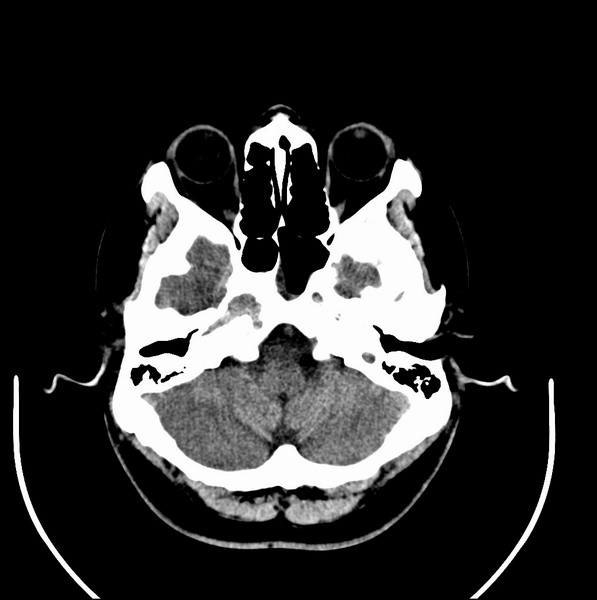

男、30、发现鼻咽部肿瘤侵犯海绵窦,未发现明显淋巴肿。请问国内那家医院治疗鼻咽部肿瘤最好?手术以何种方式为主?病灶可否全部切除?急切期待的大家的帮助。

扫描示鼻咽腔不对称,中度狭窄,右侧咽隐窝消失,局部软组织肿块,鼻咽右侧壁增厚形成肿块,突入鼻咽腔,肿块平扫呈等密度,肿块向深部侵润,右侧翼内外肌受侵,右侧咽旁间隙变窄;向后生长,头长肌界线欠清,向后上生长侵犯同侧颈动脉鞘区。双侧海绵窦增宽,内见软组织影与鼻咽部肿块相连。考虑鼻咽癌。鼻咽癌主要是放射治疗,且效果较好;到当地有治疗设备较大医院治疗即可。

这个病例有点特殊,和常见的鼻咽癌不太一样,以向颅内侵犯为主,骨质破坏区小。鼻咽癌首先要考虑,有没有其他可能?本人不会看mr片,期待有人能讲解,期待病理。

鼻咽部新生物(纤维血管瘤?鼻咽癌?)侵犯右侧中颅窝底及右侧海绵窦;建议必要时活检定性。